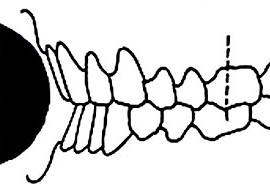

Аппарат представляет собой проволочный нёбный бюгель, который используется для стабилизации положения моляров, после лечения дистализирующими аппаратами, а так же для предотвращения потери места при лечении с удалением зубов. Жёсткая фиксация кнопки Нансе с кольцами создает прочную конструкцию для удержания достигнутого результата лечения.